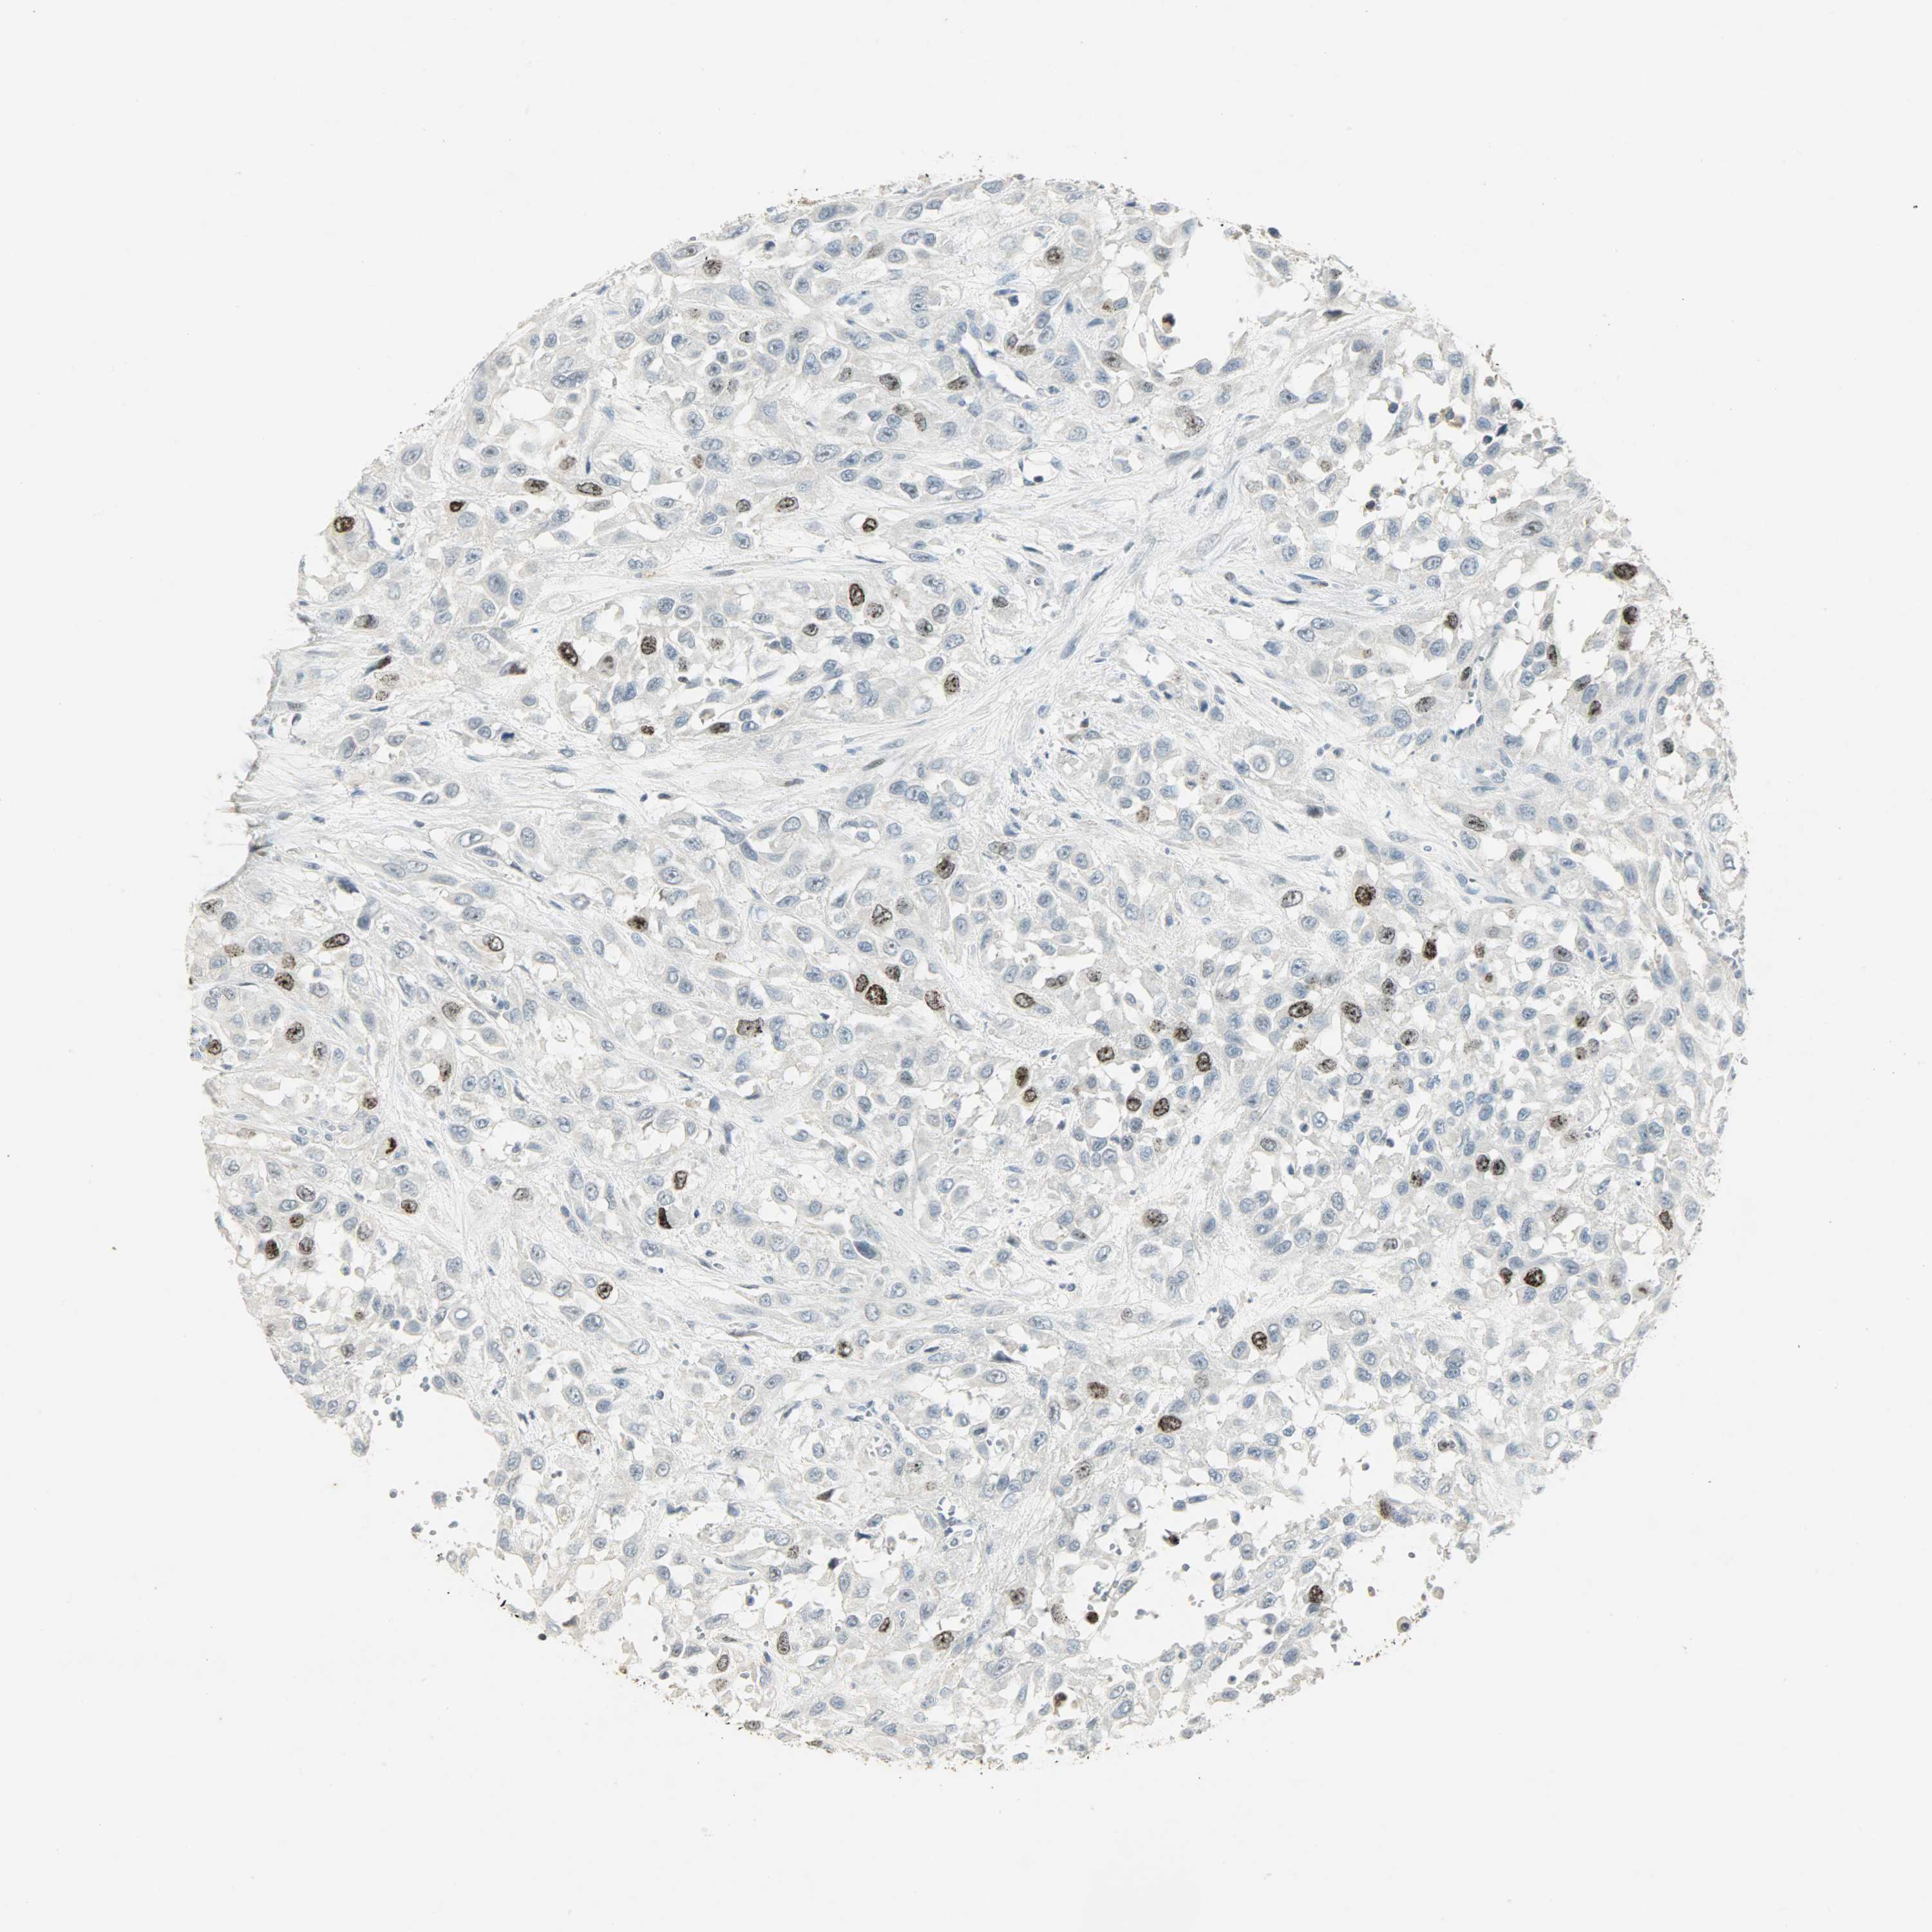

UROTHELIAL CANCER - Protein expressioni

A mouse-over function shows sample information and annotation data. Click on an image to view it in a full screen mode. Samples can be filtered based on level of antibody staining by selecting one or several of the following categories: high, medium, low and not detected. The assay and annotation is described here.

Antibody stainingi

Antibody staining in the annotated cell types in the current human tissue is reported as not detected, low, medium, or high, based on conventional immunohistochemistry profiling in selected tissues. This score is based on the combination of the staining intensity and fraction of stained cells.

Each image is clickable and will lead to virtual microscopy that enables deeper exploration of all samples and also displays staining intensity scores, fraction scores and subcellular localization as well as patient and tissue information for each sample.

Antibody CAB005862

Staining

High

Medium

Low

Not detected

Intensity

Strong

Moderate

Weak

Negative

Quantity

>75%

75%-25%

<25%

None

Location

Nuclear

Cytoplasmic/membranous

Cytoplasmic/membranous,nuclear

Urothelial carcinoma, High grade

Urothelial carcinoma, Low grade